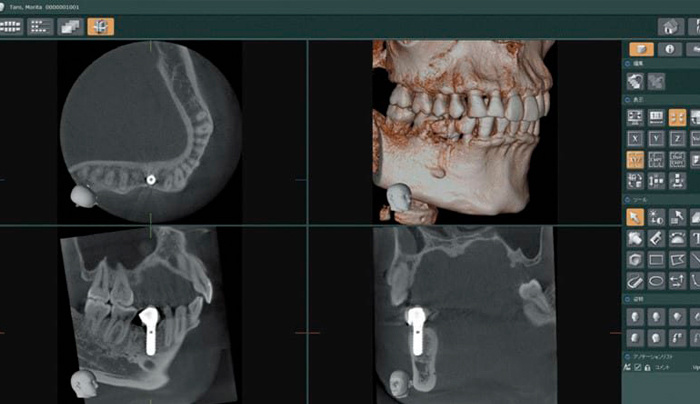

ノーベルガイドはCTスキャンで撮影した画像から起こした3D画像をもとに、コンピューターを使って作られる精巧なガイドシステムです。このガイドにはあらかじめシミュレーションで算出したインプラントの埋入場所・角度などが正確に記録され、インプラントの埋入を導きます。歯肉と骨に必要最低限の小さな穴のみを開けてインプラントの埋入を行う手術が可能なため、手術時間が大幅に短縮できて術後の後遺症も少なく、患者様への負担が少なくてすみます。